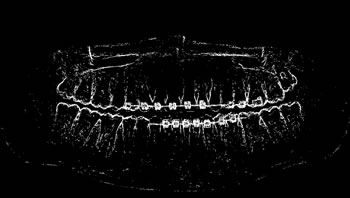

Refer to caption

Determining ROI

For each image, after the annotation of the teeth, the buccal region was also annotated, covering the whole region delineated by the contour of the jaws. This process was carried out in view of preserving the area containing all the teeth (objects of interest). Finally, the region of interest (ROI) was determined by multiplying the values of the pixel array elements, representing the original panoramic X-ray image, by its corresponding binary matrix, resulting from the process of oral annotation. Figure 5 illustrates the whole process to determine the ROI of the images.